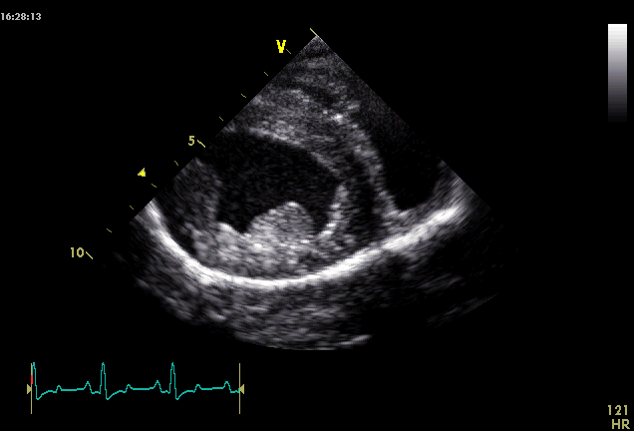

What view is this and at what level?

Right parasternal short axis view

LV @ pap mm level